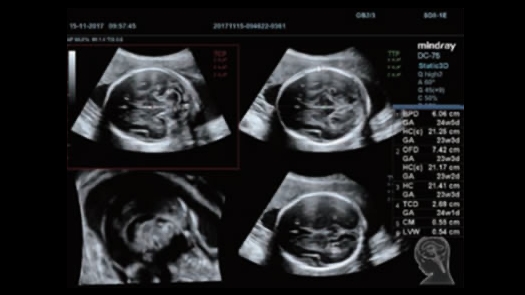

全新的DC-75以“精准”和“高效”为设计理念,基于先进的探头技术和图像优化技术,为您呈现卓越图像质量,简化操作流程,全面提升诊断信心和诊断效率,将为您带来即刻诊断、时刻轻松的工作体验,成为您在日常工作中忠实得力的诊断助手。

优异的图像质量和易获性,能够快速的帮助您完成精确的诊断

便捷的智能化操作覆盖整个检查过程,从切面获取到图像优化,从测量计算到输出报告,满足各个应用领域临床需求的同时大大提升了超声检查的效率,让您轻松应对超声日常诊断。